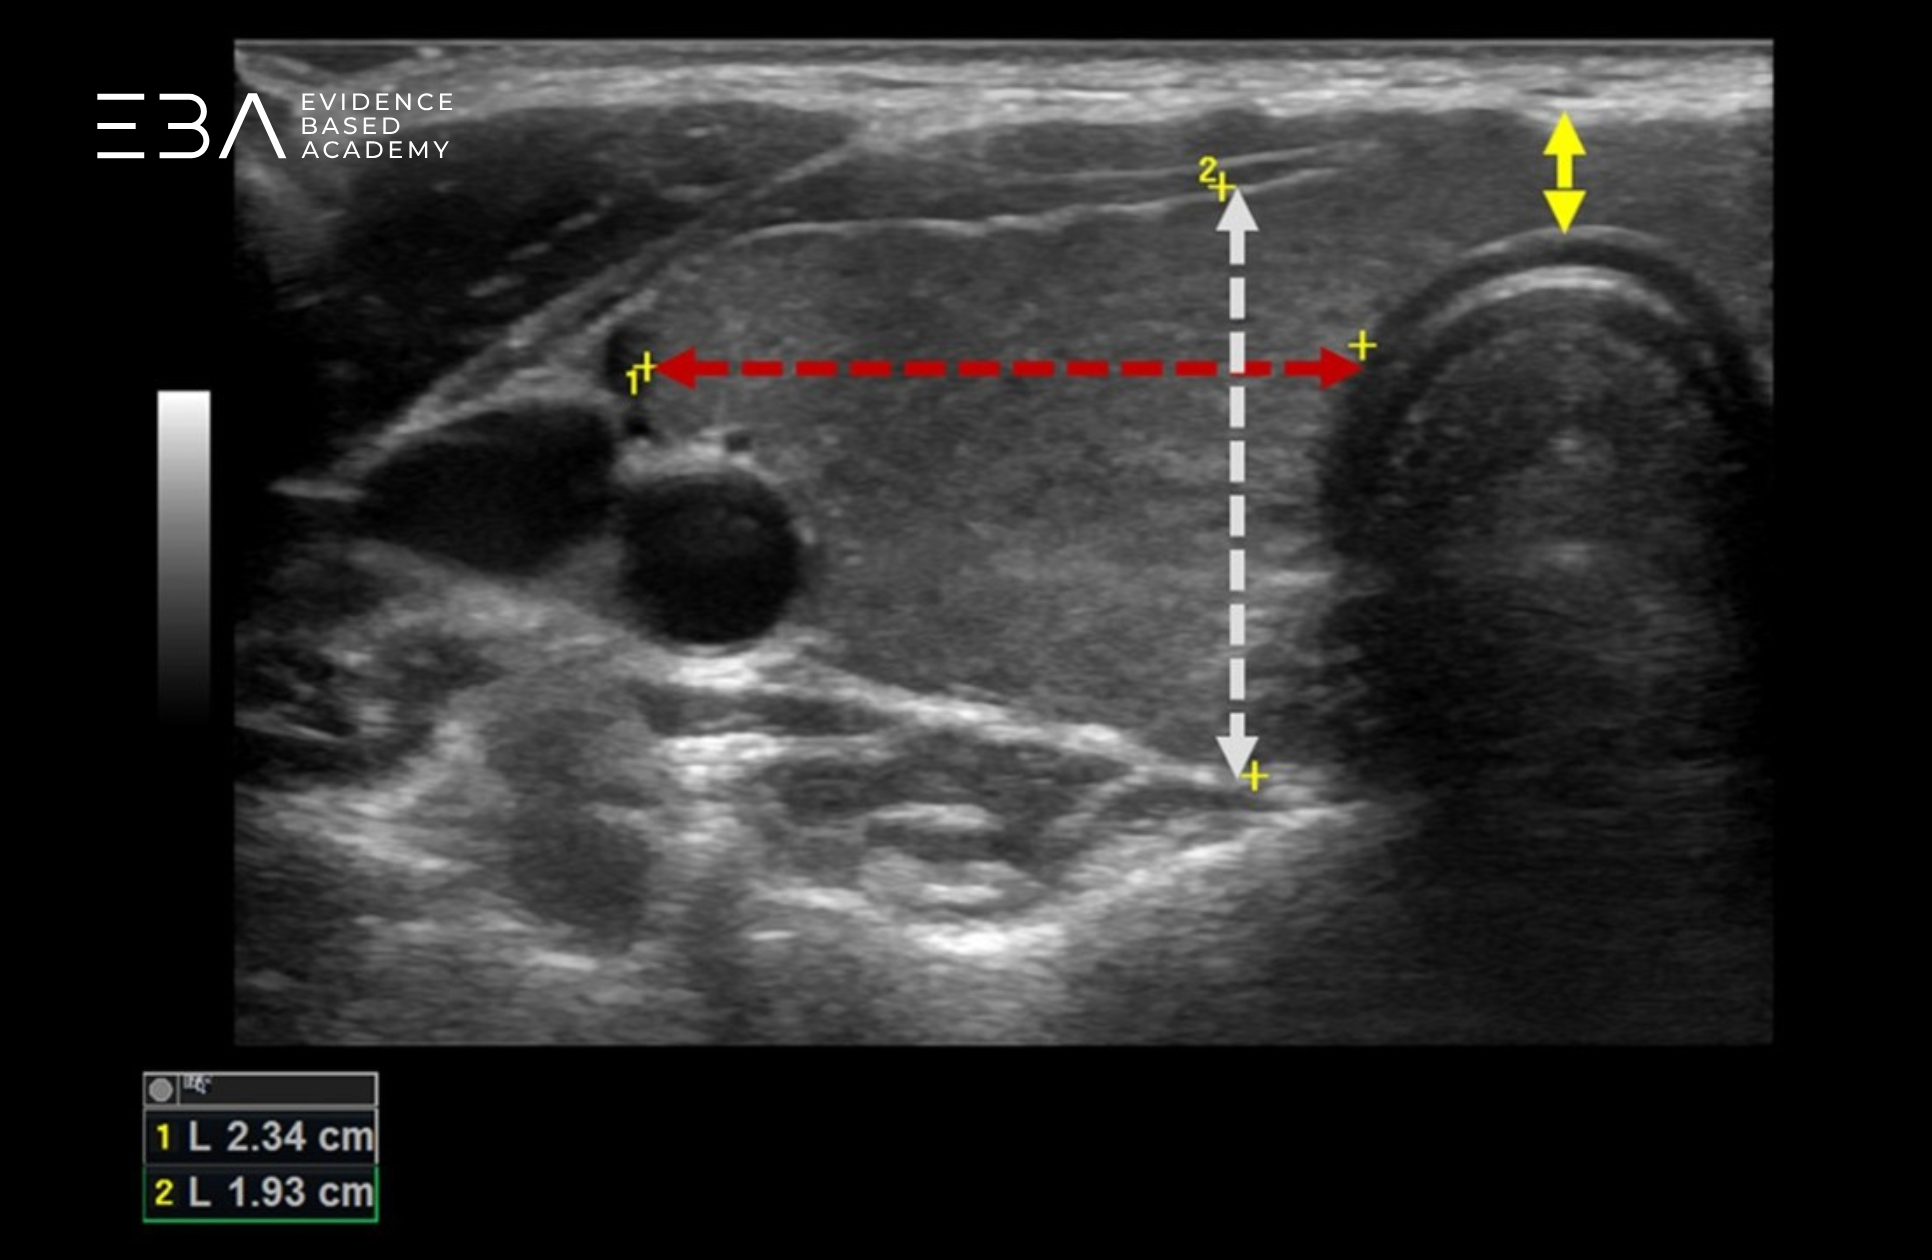

Pomiar w przekroju poprzecznym

Skanując płat w projekcji poprzecznej, wybieramy to miejsce, w którym jego przekrój jest największy. Zatrzymujemy obraz i wyznaczamy dwie odległości.

Pierwsza to szerokość płata (wymiar dwuboczny) – linia prowadzona równolegle do czoła głowicy, od bocznego do przyśrodkowego zarysu płata.

Następnie wykonujemy pomiar grubości płata, czyli jego wymiaru przednio-tylnego (anterior-posterior, AP). Początek tego wymiaru umieszczamy na grzbietowym zarysie płata w miejscu najniżej położonym na ekranie, po czym wyznaczamy linię prostopadłą względem wymiaru dwubocznego, do granicy przedniego (brzusznego) zarysu torebki.

Pomiar grubości i szerokości płata prawego w przekroju poprzecznym. Dodatkowo pomiar grubości cieśni.